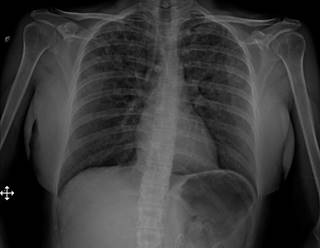

Una mujer de 47 años de edad sin antecedentes médicos se sometió a cirugía endourológica programada. Al ingreso a quirófano, se encontraba en buen estado general, con signos vitales y exploración física normales. Se aplicó anestesia general balanceada, realizando inducción con fentanilo, propofol, rocuronio y durante laringoscopia sin evidencia de anomalías. Orotubación se realizó sin complicaciones al primer intento con hoja número 3 y tubo número 7, cursa hemodinámicamente estable, sin necesidad de apoyo vasopresor con solución Hartmann intravenosa a 20 mL/h sin necesidad de mayor reanimación hídrica, ventilación de protección tidal, mantenimiento con sevorane y fentanilo en infusión calculado a 2 μg/kg/h, ventilación pulmonar simétrica y valores adecuados en capnografía postintubación. Durante el procedimiento quirúrgico sin aumento de presiones o desacoplamiento a ventilación mecánica. La paciente presentó agitación espontánea al recobrar conciencia realizando esfuerzos inspiratorios importantes con laringoespasmo breve de cuarenta segundos. La extubación presentó disminución de agitación y sin deterioro del patrón respiratorio; durante la hora de vigilancia postoperatoria, sin deterioro cardiorrespiratorio. Sin embargo, dos horas posteriores a extubación, la paciente mostró signos de dificultad respiratoria: taquipnea, uso de musculatura accesoria, desaturación al 70% al aire ambiente, estertores crepitantes bilaterales; radiografía de tórax portátil reveló evidencia de edema agudo pulmonar (Figura 1). La administración de oxígeno suplementario logró aumentar saturación hasta 92%. Ante sospecha de edema pulmonar de presión negativa, se realizaron ecocardiograma transtorácico y angiotomografía de tórax, sin evidencia de falla cardiaca ni tromboembolia pulmonar. Se optó por utilizar puntas nasales de alto flujo, diurético de asa, nebulizaciones con β-agonistas y terapia pulmonar. La paciente evoluciona de manera satisfactoria (Figura 2), dándose de alta al tercer día postoperatorio.

Figura 2: Radiografía de tórax anteroposterior. Resolución edema agudo pulmonar.